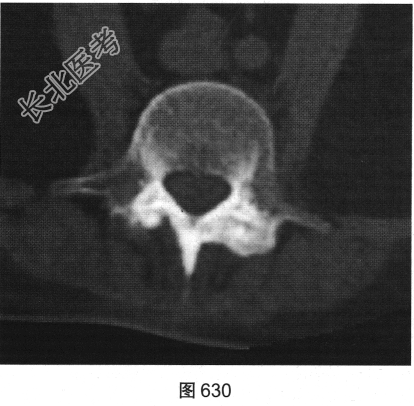

- 多项选择题2.[提示]患者行脊椎及骶髂关节CT检查,见图629~图631。该患者CT图片有哪些阳性征象( )

D、椎旁韧带骨化

E、胸腰段后凸畸形

F、双侧骶髂关节及脊椎椎小关节间隙消失

G、竹节椎